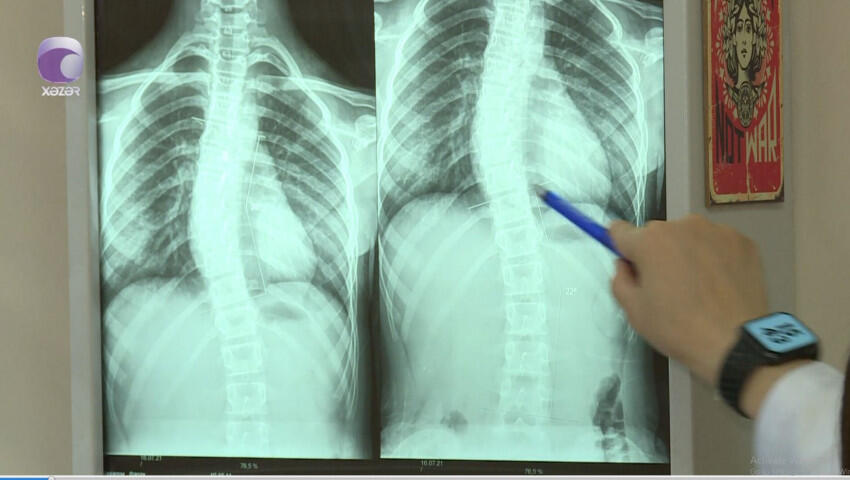

"Son zamanlar 8-12 yaş aralığındakı uşaqlarda bel və boyun ağrıları ilə bağlı şikayətlər nəzərəçarpacaq dərəcədə artıb.

Halbuki, illər öncə uşaqlarda belə problemlər olmurdu. Bunu fizioterapevt Səidə Kərimova "Xəzər xəbər"ə müsahibəsində deyib.

Son.az xəbər verir ki, həkim səbəb olaraq bildirdi ki, uşaqların çantaları kifayət qədər ağırdır. Çiyin ağrıları isə xüsusən ona görə yaranır ki, ağır çantaları daşıyarkən, kəmərləri uşağın yumşaq toxumasını sıxıb kəsir.